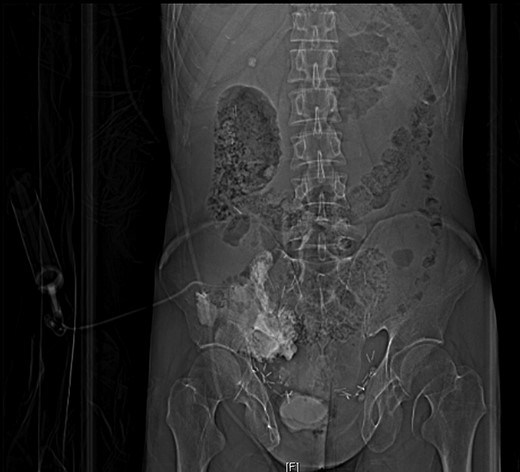

A 44-year-old male presented to Addenbrookes Hospital Accident & Emergency (A&E) Unit with two hours of abdominal pain, generalized distress, and peritoneal signs on physical exam. He has a history of extrophy-epispadias complex repaired as an infant. Due to persistent incontinence at the age of 36 years, he underwent cystectomy and formation of a cecal pouch with continent catheterizable appendiceal channel in the right lower quadrant. The patient reports catheterizing regularly with a 14Fr catheter, but was unable to catheterize the pouch for 8 hours prior to presentation. Notably, the abdominal pain became severe after a cough at home. In the A&E unit, the channel was catheterized with a 12Fr catheter with 150 mL of urine drainage. An initial non-contrasted CT of the abdomen and pelvis demonstrated a large amount of free fluid within the abdomen. The CT was repeated with contrast injected into the pouch via the 12Fr catheter, which demonstrated an intraperitoneal rupture (Figs 1 and 2). The patient was taken emergently to the operating theatre and a midline laparotomy was performed. The rupture in the cecal pouch was 1 cm in diameter, located on the anteromedial and inferior aspect of the pouch, and repaired with 2-0 polyglactin suture in two continuous layers (Fig. 3). The pouch was water-tight on leak test with 600 mL of normal saline. The pouch was kept to continuous drainage with a 14Fr Foley through the continent catheterizable channel. The Foley placement was confirmed intraoperatively by palpating the catheter in the pouch. A peritoneal drain was placed in the left lower quadrant. The midline fascia was closed with continuous 1-0 non-absorbable monofilament suture and the skin was closed with 3-0 polyglactin suture. The patient was taken to intensive care postoperatively and made an uneventful recovery.